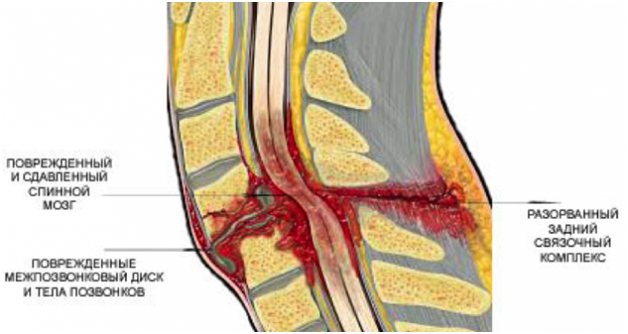

Повреждение позвонка со сдавливанием спинного мозга и отеком

Отек позвонка чаще всего происходит при травмах или разрушениях кости

Переломы и ушибы влекут за собой увеличение жидкости в костных пластинах позвоночника, которая нарушает кровообращение. Если продолжительное время ничего не предпринимать, это приведет к разрушению костных тканей и отекам.

Субхондральный отек позвонков может сопровождаться полным или частичным нарушением чувствительности конечностей, их полным обездвиживанием. При травмах и воспалении шейных позвонков нарушается дыхание из-за атрофии дыхательной мускулатуры, сосуды утрачивают свой тонус. Если у человека возникают сложности с дыханием, необходимо немедленно обратиться в медицинское учреждение.